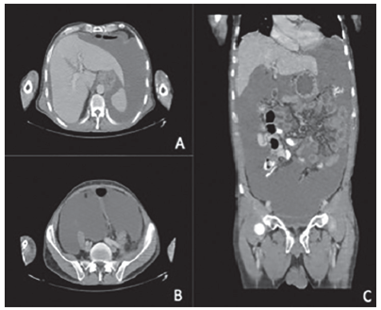

En la primera consulta en el Instituto Nacional de Cancerología, el paciente se encontraba en regulares condiciones generales, con desnutrición leve y aumento del perímetro abdominal por ascitis. En la tomografía computarizada (TC) de abdomen con contraste que le había sido tomada, se apreciaba ascitis, alteración de la densidad de la grasa mesentérica y realce difuso del peritoneo.

Con los estudios de extensión, se descartó enfermedad extraperitoneal y se calculó un índice de carcinomatosis peritoneal (Peritoneal Cancer Index, PCI) de 15 mediante la TC (figura 2) y de 21 por laparoscopia.